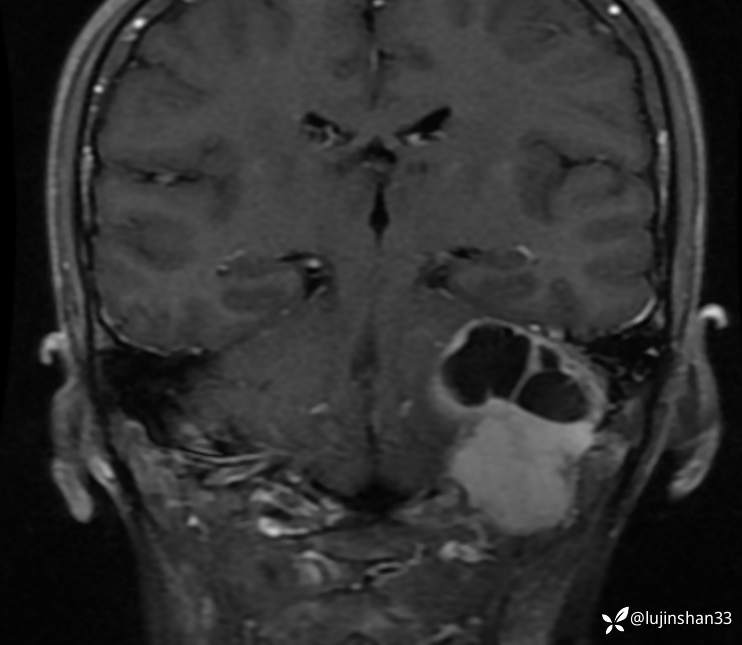

半年后复查

术后1年半复查CT及MRI

【现病史及既往史】:患者2年前无明显诱因出现左耳搏动性耳鸣、听力下降,耳鸣持续存在,伴轻度头晕,无眩晕及恶心、呕吐,无左侧外耳道流脓、流血,无视力下降,于2018-09-19在XXX市第一人民医院行颞骨CT及颅脑核磁示:左侧岩骨-桥小脑角区占位性病变,伴骨质破坏,考虑肿瘤性病变,于2019-02-19日于在我科住院行“经枕颈联合径路颞骨、颈静脉球窝及后颅窝肿瘤切除+腹部脂肪取出术腔填充+外耳道封闭”,病理结果(2019-2-19,我院)(左颞骨、左颞骨后颅窝、后颅窝硬脑膜) 富于破骨样巨细胞的肿瘤,背景为基质细胞梭形,界限不清,部分区域可见出血,局部见反应性骨形成,考虑为骨巨细胞瘤。送检瘤组织大小分别为1.2x1.2x0.7cm、7x6x2.5cm、3x2x0.8cm。(左颈部)淋巴结未见转移肿瘤(0/2)。免疫组化结果:p63(部分+),SATB2(+),Ki-67(+10%)。术后定期门诊随访,于2019-09-02行颞骨CT示:左侧颞骨骨巨细胞肿瘤术后改变,左后颅窝异常强化灶累及左侧颞骨斜坡,考虑复发,为进一步手术治疗来我院,以"颞骨骨巨细胞瘤术后(左)"收住入院。